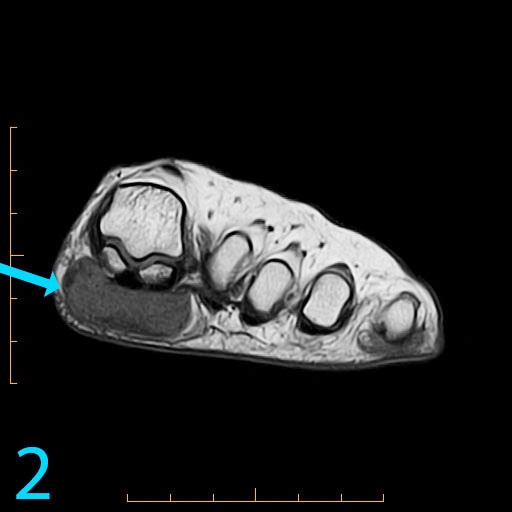

This 18-year-old female presents with a palpable soft tissue mass subjacent to the first metatarsophalangeal (MP) joint that she has noticed for 1-2 months. It is painful with shoes and ambulation, and you are evaluating her for a soft tissue tumor. What is the cause of her problem, and what pertinent negatives must you notice?

This patient has a so-called "pressure lesion" due to ambulation, with associated adventitial bursa/pseudobursa formation within. It is a chronic process. This is manifested as a large, ovoid mass-like structure within the subcutaneous soft tissues along the plantar aspect of the first MP joint and sesamoid bones (arrow). It is well-circumscribed and demonstrates a mildly lobulated configuration. There is peripheral signal hypointensity indicating a rim or rind of fibrosis, and there is intermediate to high T2 signal centrally, suggesting a component of complex fluid. The major differential diagnosis is fibroma of tendon sheath. This is a counterintuitive diagnosis as fibrous lesions are typically dark on all pulsing sequences. But, fluid signal from the tendon sheath may be found in this specific fibrous tumor. So, fibromas of tendon sheath are typically hyperintense centrally.

While the lobulation of the lesion medially is reminiscent of plantar fibromatosis, the constellation of findings remains most compatible with a giant pressure lesion. Fibromatosis (non-aggressive type) occurs more proximally in the middle aponeurotic cord of the plantar fascia. The findings are not suspicious of an aggressive neoplastic lesion (based on location and concentric shape), and you can also rule out MP joint capsulitis and Morton's neuroma because of location. You should always rule out plantar plate tear along the second MP joint on thin section sagittals if you have a large pressure lesion under the second metatarsal head. For more case review, visit MRI Online.